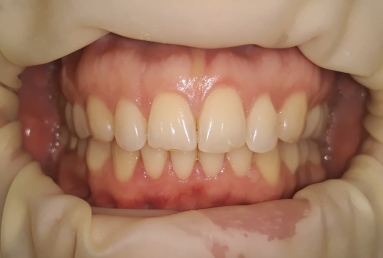

SAPPHIRE ORTHODONTIC DEVICE

Orthodontic treatment, external sinus lifting, dental implant and zirconium crown.